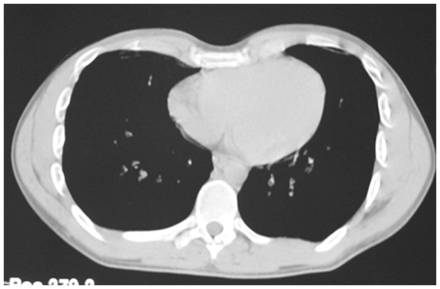

Клинический пример: внешний вид пациента 21 года с воронкообразной деформацией грудной клетки 1 степени

Операция: коррекция ВДГК эндопротезированием

Результат хирургической коррекции воронкообразной деформации грудной клетки эндопротезированием